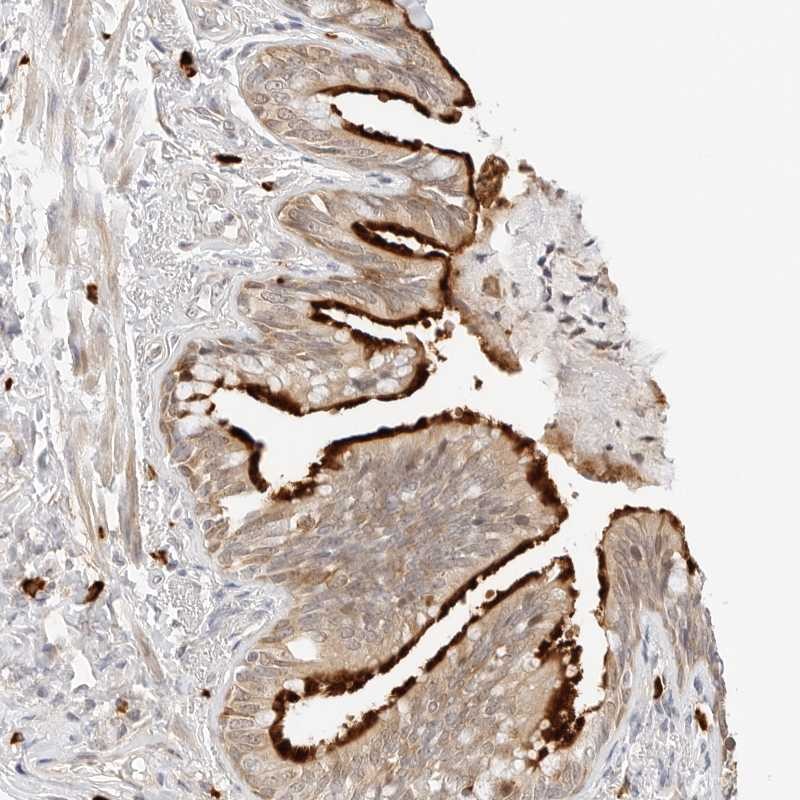

Immunohistochemical staining of human bronchus shows strong membranous positivity in respiratory epithelial cells.